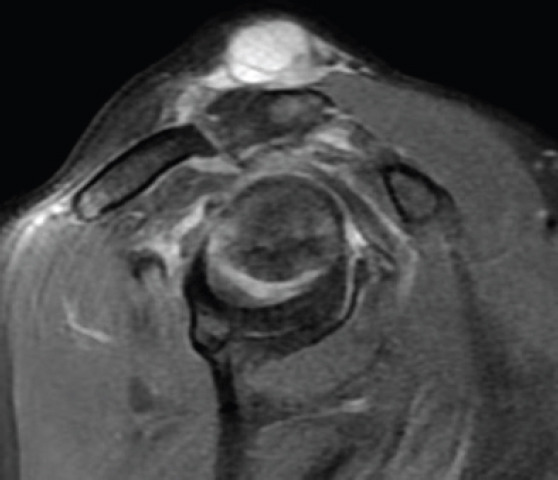

Case report: We present to you a 77-year-old male patient with hypertension and diabetes, who came with a painless swelling over the right shoulder, gradually increasing in size for the first 6 months. He gave a prior history of pain in the shoulder associated with stiffness, depicting a frozen shoulder 5 years ago. On examination, the swelling was soft, cystic, non-reducible, fluctuant, measuring 3 × 3 cm centred over the AC joint. The range of motion was near normal, comparable to the opposite side, associated with crepitus, although pain free. Clinical special tests revealed intact but weak cuff muscles. Imaging was performed that revealed superior migration of the humeral head and near complete chronic supraspinatus tear with glenohumeral arthritis on radiograph. Magnetic resonance imaging showed synovial thickening with a cystic homogenous swelling above the AC joint, a cutoff geyser sign with no communication to the AC joint or subacromial bursa. Complete excision of the cyst in toto was performed with no additional procedure. The histopathological examination revealed a ganglion cyst.